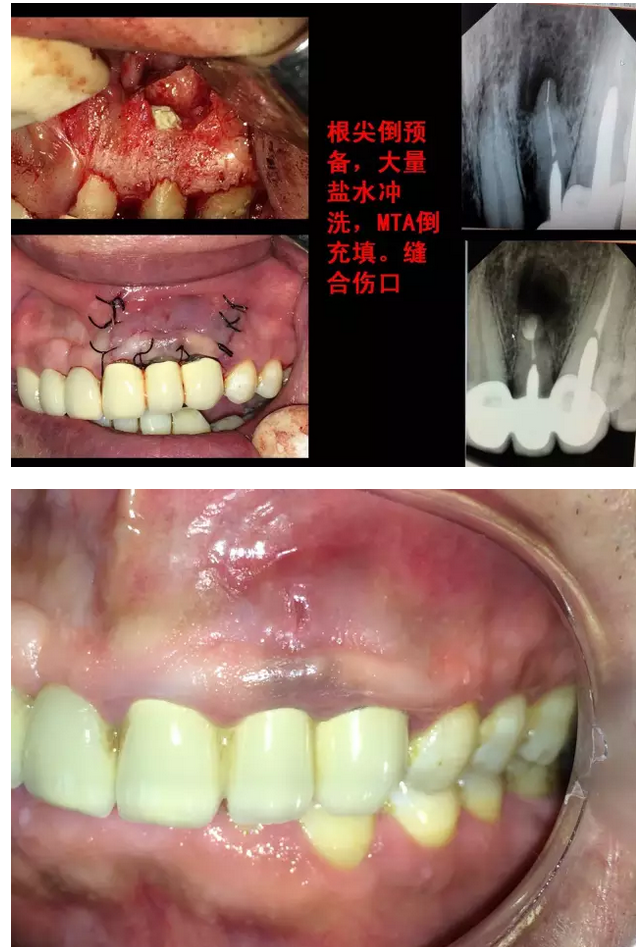

兩例根尖手術(shù)病例欣賞

來源于牙醫(yī)世家